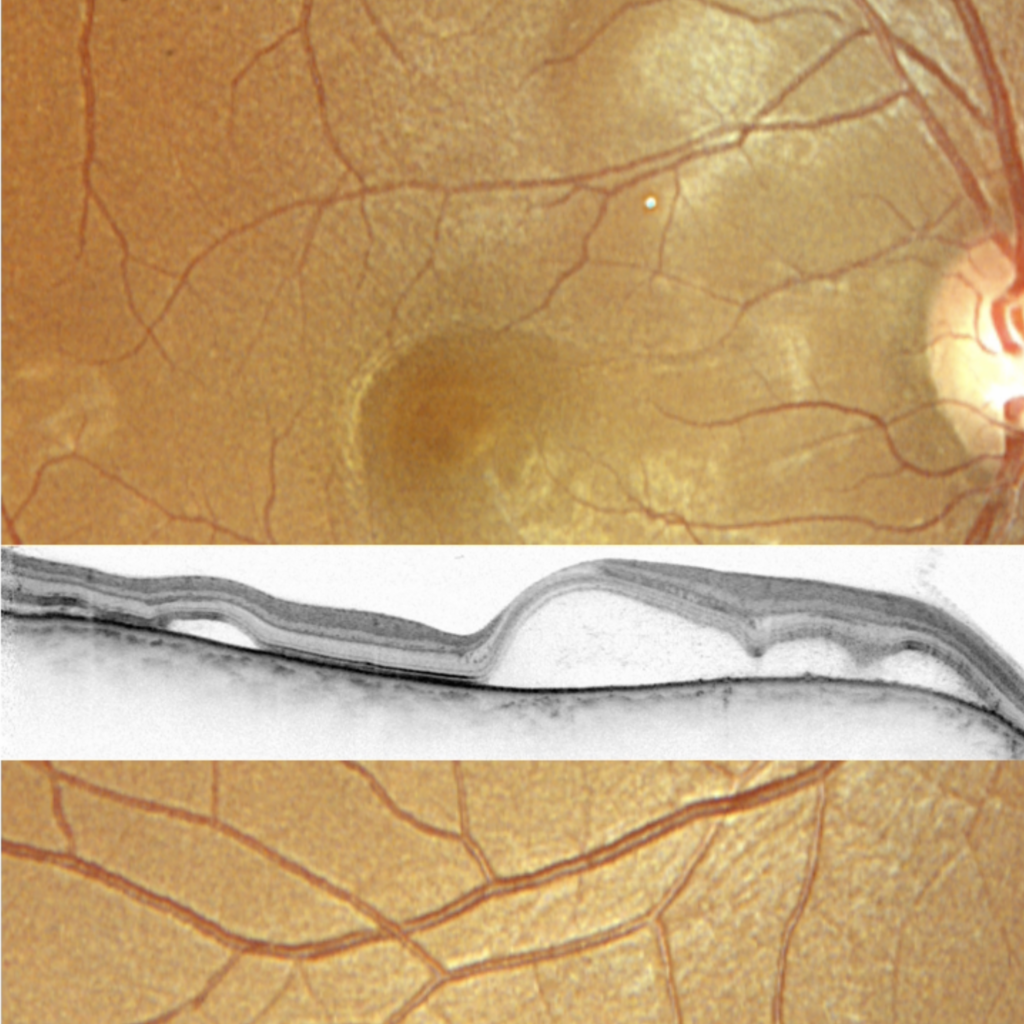

Myopie forte

OCT d’un staphylome postérieur, complication typique de la myopie forte.